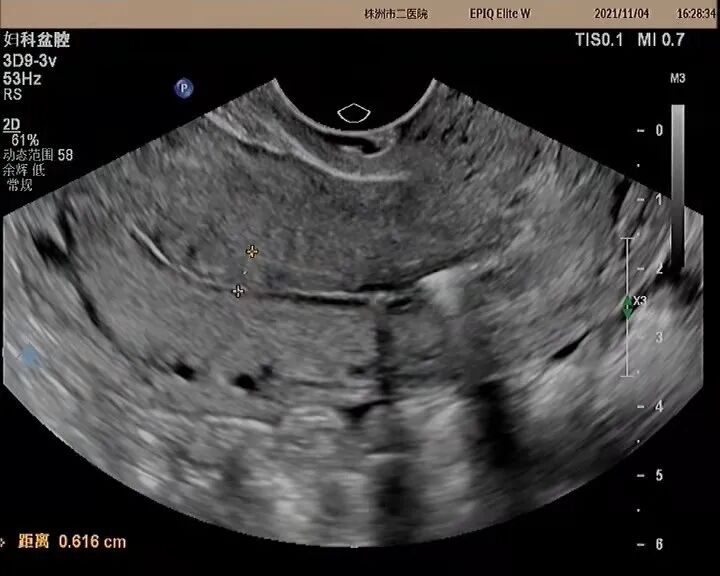

近一兩月,月經(jīng)延長,淋漓不盡,才急急忙忙來到醫(yī)院檢查。一打彩超,好家伙節(jié)育器都跑到宮頸內(nèi)口了,宮腔還被一個“壞蛋”給“占領(lǐng)”了。

常規(guī)二維

常規(guī)二維超聲基礎(chǔ)上聯(lián)合三、四維超聲,可以進(jìn)一步明確宮內(nèi)節(jié)育器的空間位置和形態(tài),判斷是否存在節(jié)育器嵌頓及移位等,能提供更準(zhǔn)確診斷,并提供更多患者宮腔形態(tài)信息,除明確診斷外,還有更廣泛的臨床應(yīng)用價值。